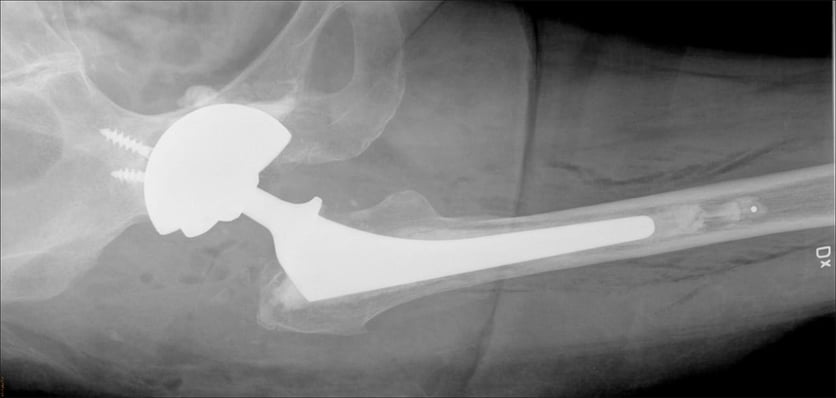

Vid omoperation av höftproteser kan risken för instabilitet minska med en metod där man cementerar fast dubbelskålar i en större metallskål, CMC-metoden.

– Vid omoperation av lösa höftproteser använder man sig ofta av stora skålar av metall. Detta kan leda till att höftprotesen hoppar ur led vilket är mycket smärtsamt och ofta kräver ytterligare operationer. En ny metod som utvecklats här på Akademiska sjukhuset innebär att man cementerar fast dubbelskålar i en större metallskål, vilket minskar denna risk, säger Anders Brüggemann, ST-läkare i ortopedi, Akademiska sjukhuset, som lett studien som publicerats i den vetenskapliga tidskriften Acta Orthopaedica.

Studien baseras på data från det loka höftprotesregistret i Uppsala och omfattade patienter som genomgick byte av höftledsprotes mellan 2008 och 2016. Totalt följde man upp 184 höftledsbyten på män och kvinnor i åldern 35-88 år (genomsnittsåldern var 67 år). Forskarna jämförde utfallet av två metoder, en där man cementerat fast dubbelskålar, så kallad DMCs, i en större metallskål, och en där man använde en enklare plastskål insatt i metallskålen.